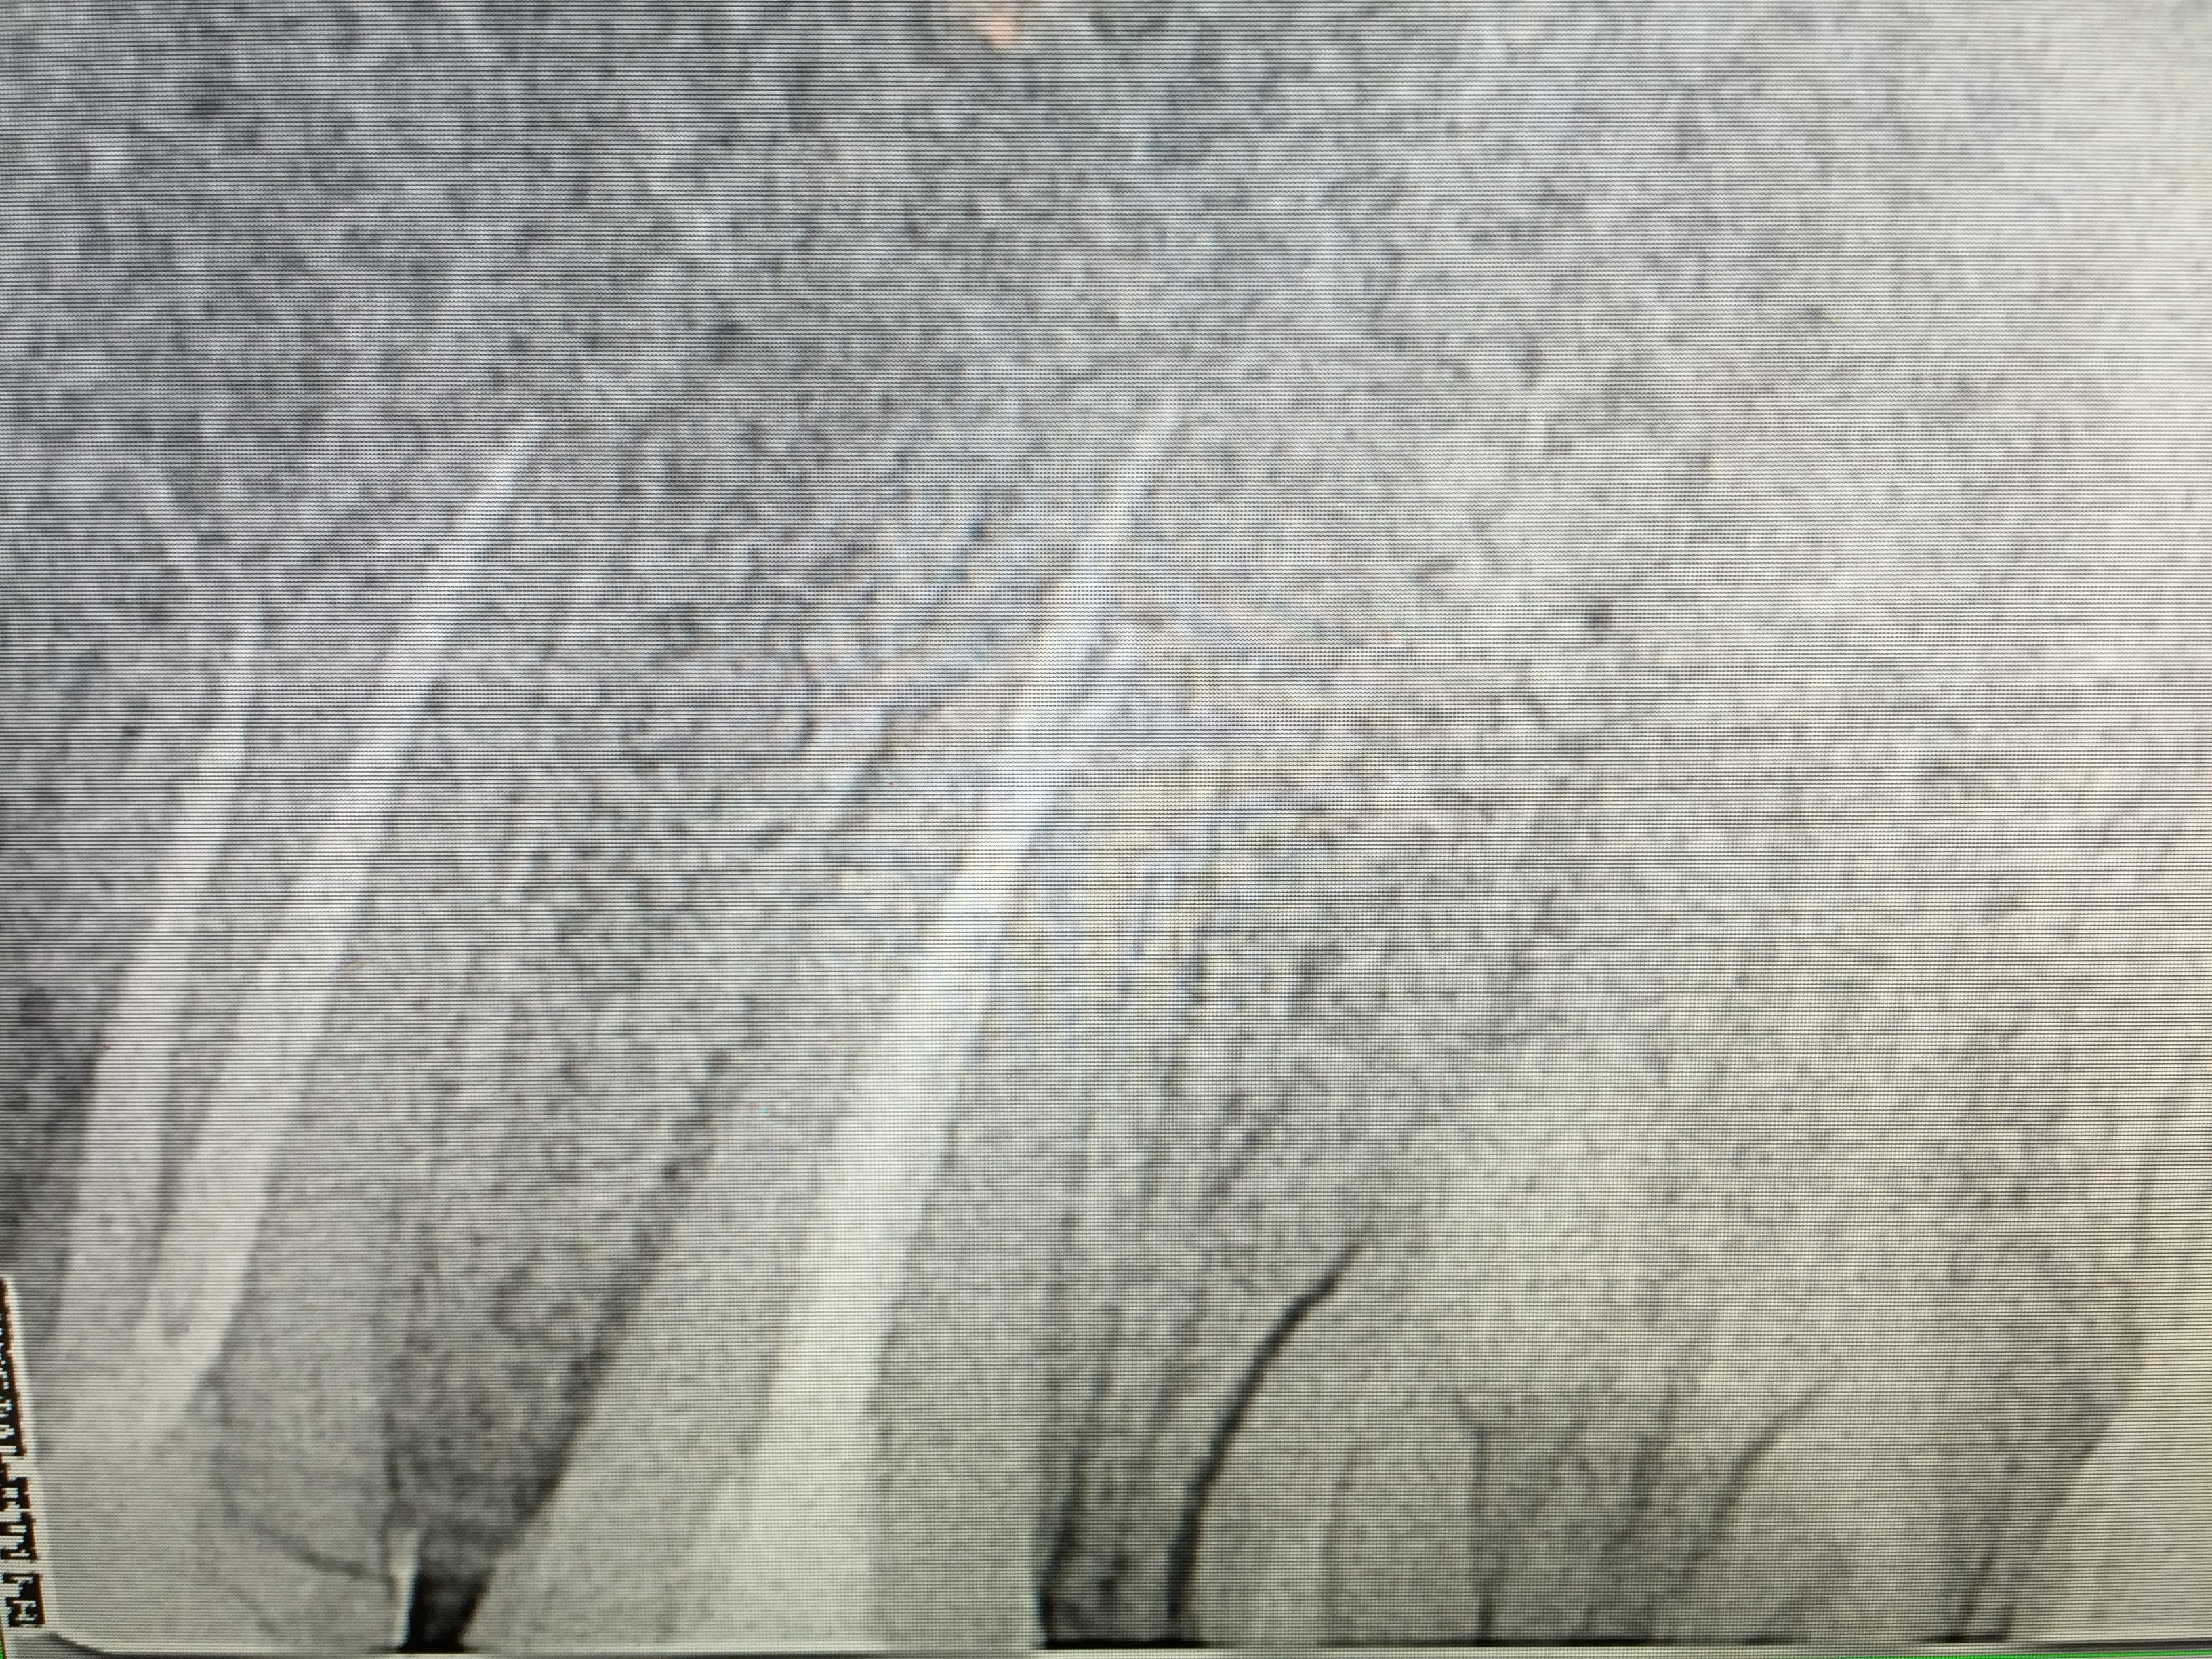

Historique de la 17 de ma femme.

Tu as raison des fois on y peut rien. J'aurais du l'extraire. -))))

Mais bon 33,44 pour une extraction ca ne rapporte pas assez. -)))